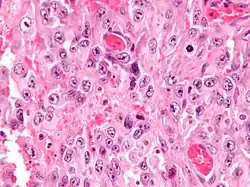

| Micrograph of an epithelioid sarcoma. H&E stain. | |

Histologically, epithelioid sarcoma forms nodules with central necrosis surrounded by bland, polygonal cells with eosinophilic cytoplasm and peripheral spindling.[3] Epithelioid sarcomas typically express vimentin, cytokeratins, epithelial membrane antigen, and CD34, whereas they are usually negative for S100, desmin, and FLI1 (FLI-1).[3] They characteristically lack the protein INI1 (see below). Epithelioid sarcomas typically stain positive for CA125.[4]